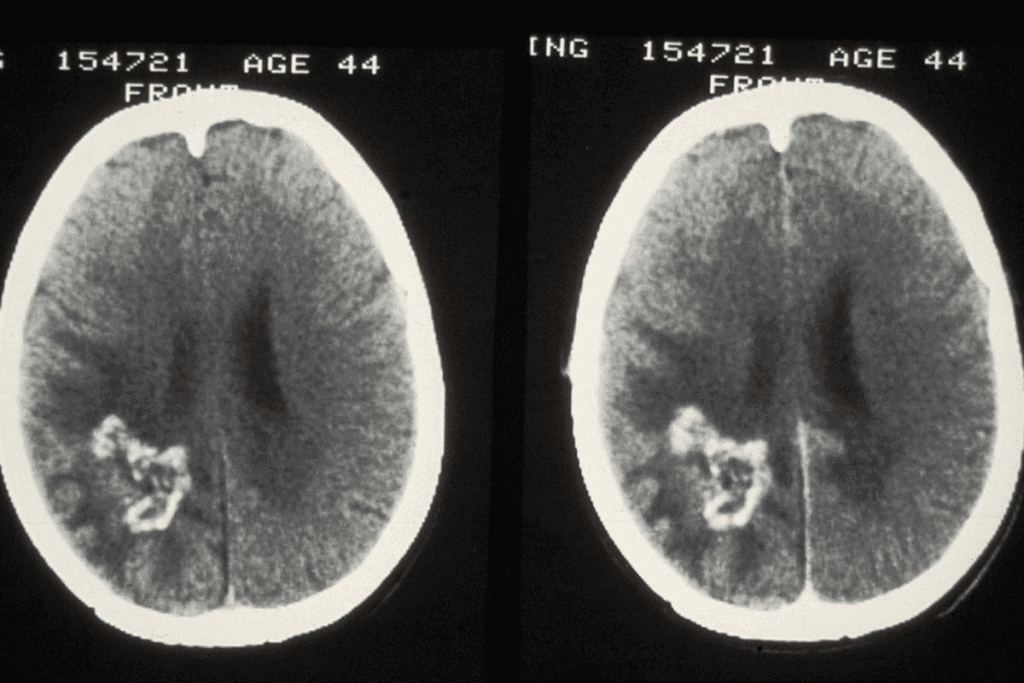

Imaging Tests for Brain Tumor Detection

Imaging tests are key in finding brain tumors. The main ones used are:

- Magnetic Resonance Imaging (MRI): MRI gives detailed brain images. It helps find the tumor’s size and how it affects nearby areas.

- Computed Tomography (CT) Scan: CT scans are fast and useful in emergencies. They show if there’s a tumor and if there’s bleeding or calcification.

- Positron Emission Tomography (PET) Scan: PET scans help tell tumor types and check metabolic activity. This helps plan treatment.

Biopsy and Other Diagnostic Procedures

Often, a biopsy is needed to confirm the diagnosis and find the tumor type. This means surgically removing a tumor sample for lab tests.